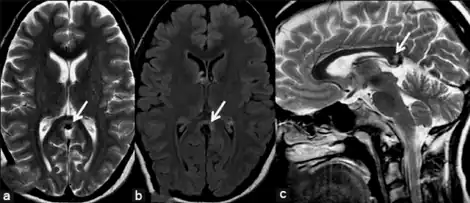

MRI with a) hemicrania continua, showing semilunar hyperintensity, b) fluid attenuated inversion recovery images, c) with a focal hyperintensity on sagittal T2-weighted image